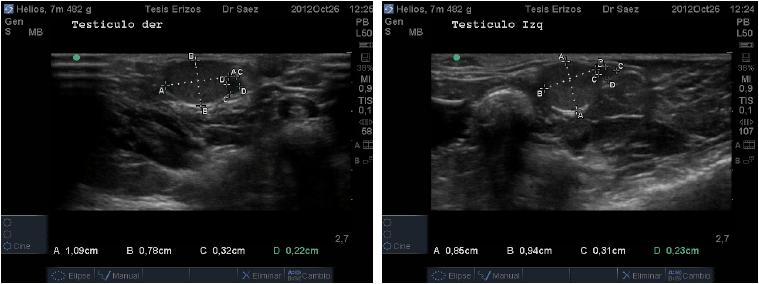

Topográficamente los testículos de los ETA se encuentran intra abdominales, vía ecográfica se observan caudo-ventralmente en el abdomen caudal y ubicados dentro de los recesos para-anales. El órgano presentó forma circular en el corte transverso, en la parte media, a diferencia del corte longitudinal donde se observaron ovalados. Su eje largo presentó una ligera oblicuidad siendo dorso-craneal/caudo-ventral. Su parénquima se presentó de mediana ecogenicidad, granulado fino y homogéneo. No se visualizó la línea ecogénica que describió Nyland [7] en el interior del testículo de animales domésticos, que correspondería al mediastino testicular (FIG. 4), esto podría deberse a que probablemente el mediastino en esta especie es menos fibroso o podría ser menos desarrollado y ubicarse en el extremo craneal del testículo, tal como ocurre en el equino (Equus caballus). Sería recomendable realizar un estudio morfoestructural para confirmar esta observación.

Los resultados cuantitativos de morfometría fueron medidos en centímetros (cm) y expresados en promedios junto con desviación estándar (X ± DE). Se midió ancho, alto y largo de Testículo Izquierdo, y Testículo Derecho. En el caso del Epidídimo se midió ancho y alto de epidídimo en diez machos, ya que en uno de los pacientes no fue observable. En el 80% de los casos en el epidídimo predominó el ancho sobre el largo. Se midió el ancho, alto y largo de la Próstata. Los resultados se especifican en la TABLA III.